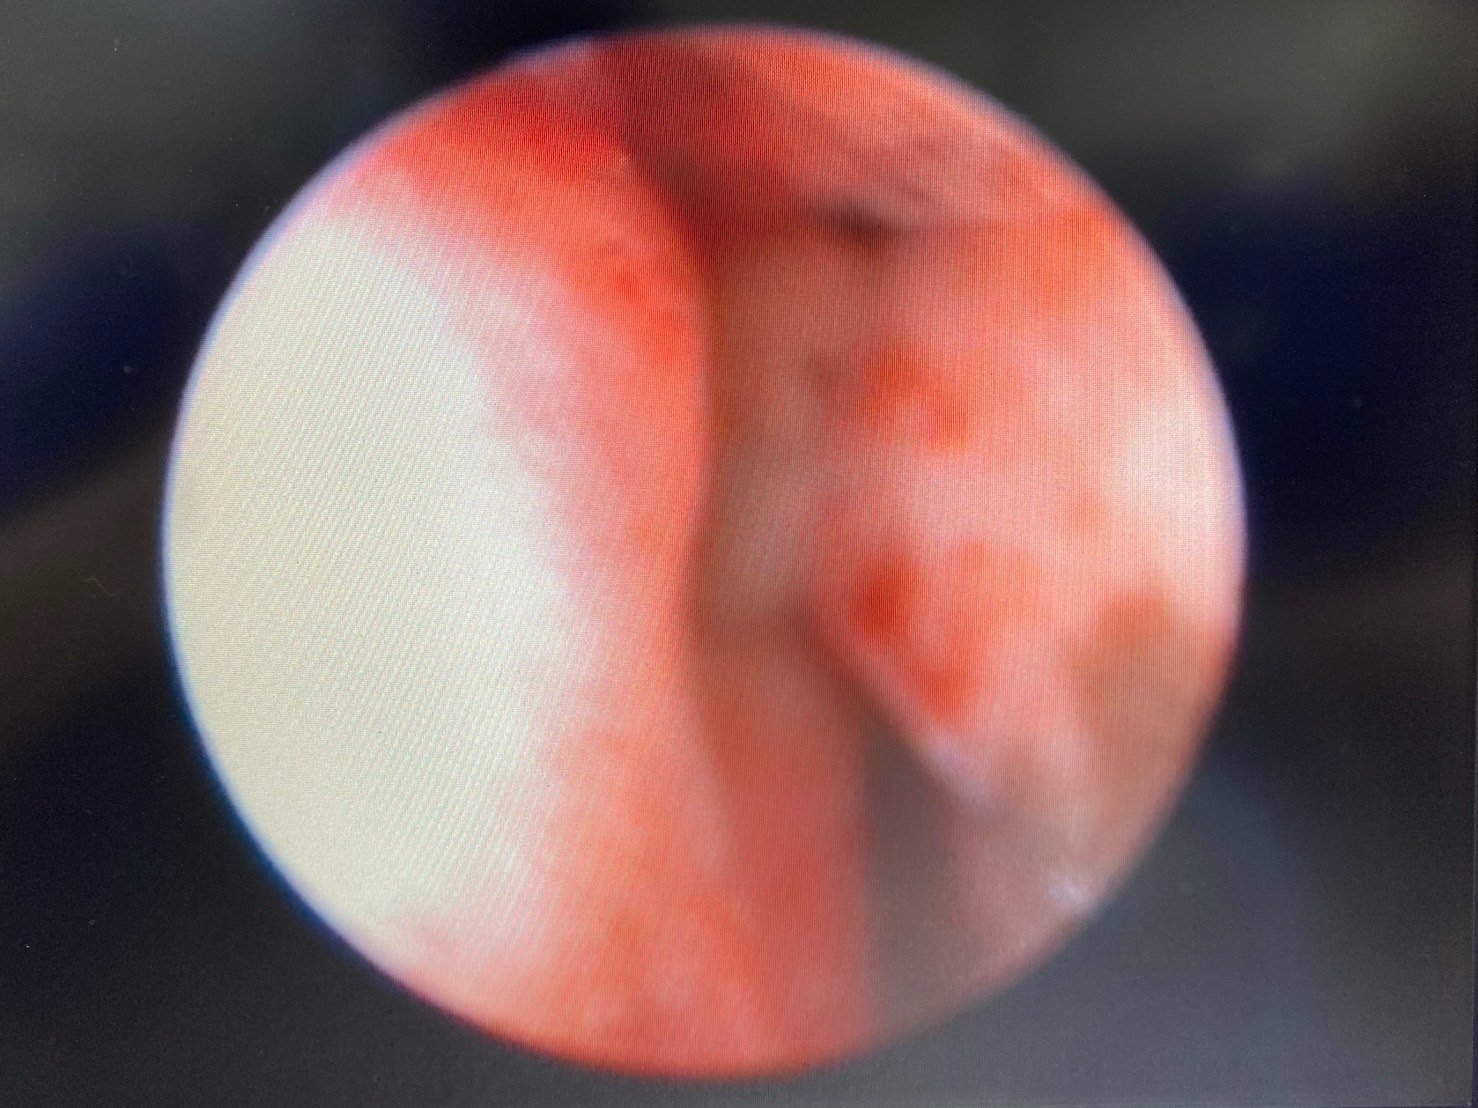

柴犬皮皮因長期有鼻塞、流鼻血、流鼻水的症狀來築心就診,在這之前已經換過兩間醫院,但治療效果都不太好。在一系列的評估後,我們為皮皮安排了電腦斷層以及鼻腔內視鏡的檢查,檢查後發現在皮皮的鼻腔內有疑似腫瘤的團塊,並且向後侵入鼻竇,甚至已經接近大腦。我們運用內視鏡設備採樣取得了團塊的切片,並得到鼻上皮細胞癌的診斷。